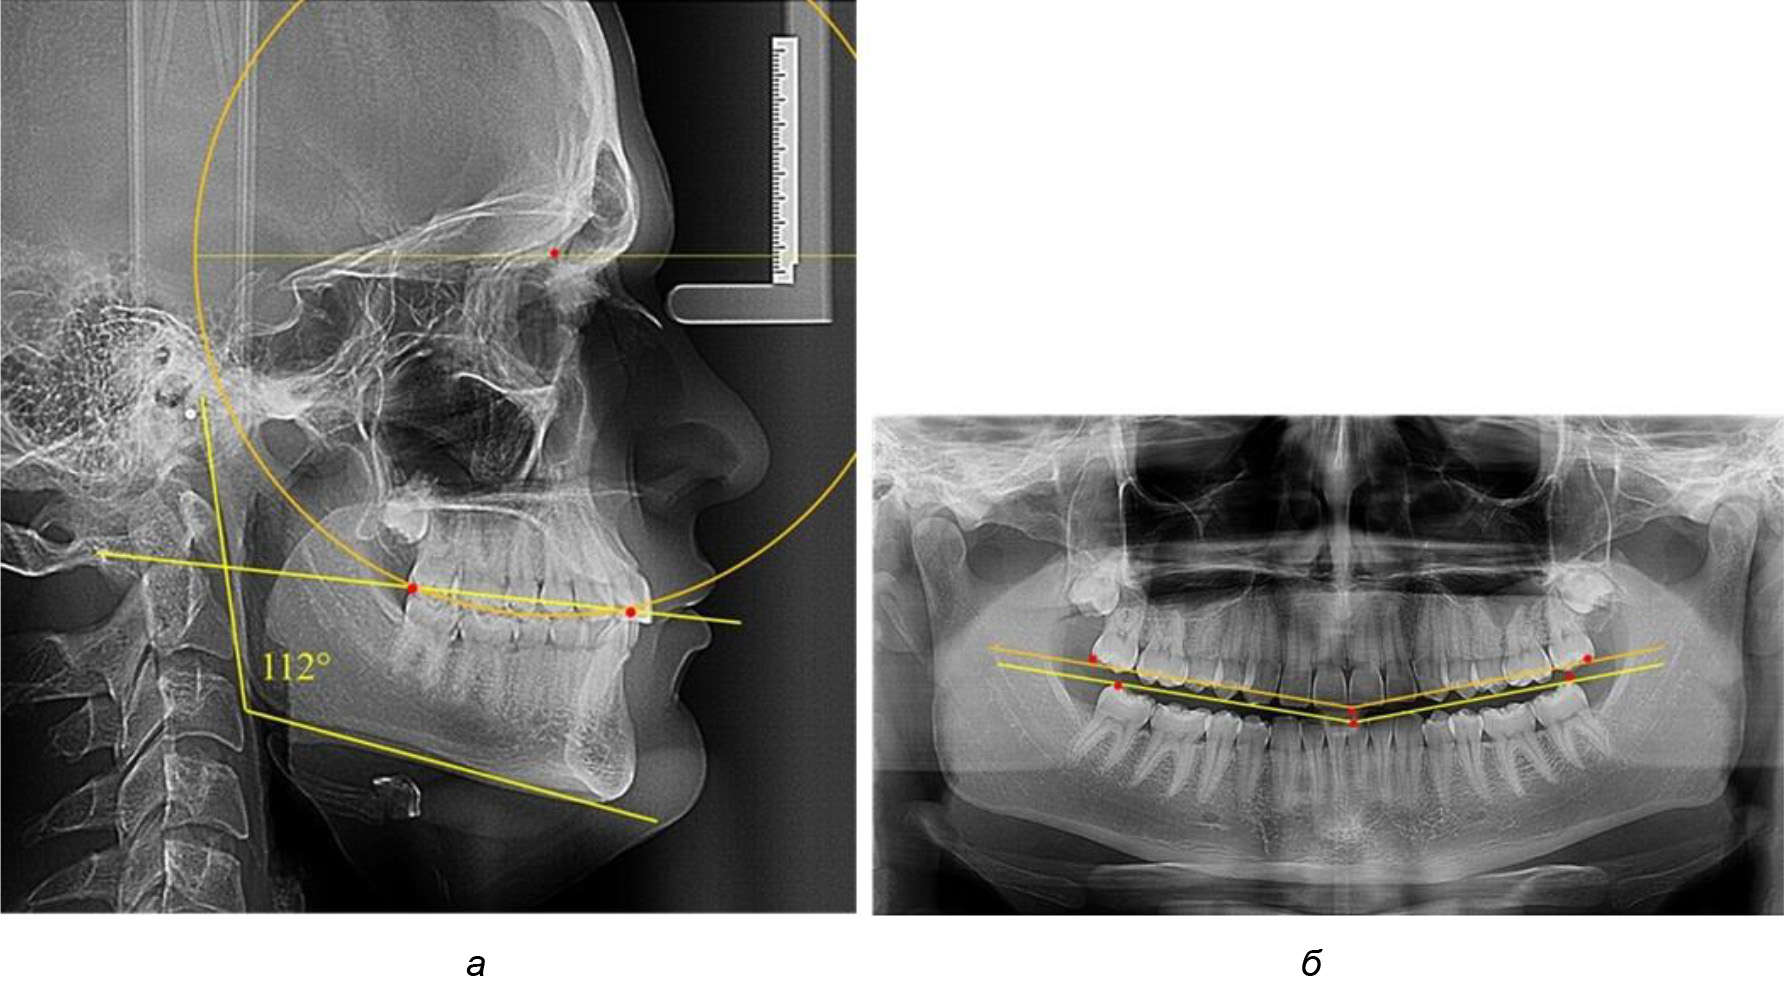

В 3-ю подгруппу вошли ТРГ и ОПТГ 14 человек 1-й группы, что составило (22,58 ± 5,31) % от общего количества людей 1-й группы. Величина угла нижней челюсти в среднем составила (114,85 ± 2,87)° и характеризовала горизонтальный тип нижней челюсти.

Глубина кривой Spee в среднем по 2-й подгруппе составил (2,94 ± 0,47) мм, что было меньше, чем в других подгруппах. Деление величины радиуса круга к длине окклюзионной линии составило 1,616 ± 0,02 (рис. 4).

Рис. 3. Особенности кривой Spee на ТРГ (а) и ОПТГ (б) при нейтральном типе роста нижней челюсти

Рис. 4. Особенности кривой Spee на ТРГ (а) и ОПТГ (б) у людей с горизонтальным типом лица